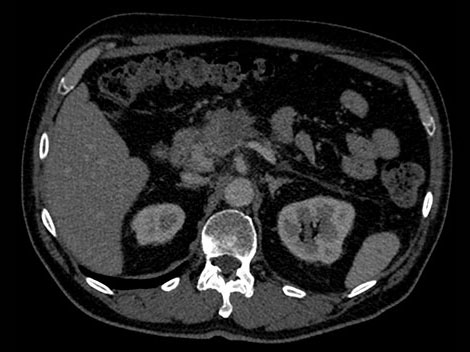

W celu zobrazowania możliwości tomografu komputerowego z detektorem spektralnym prezentujemy dwóch hipotetycznych pacjentów o takim samym profilu zdrowotnym, narzekających na ból brzucha. Ich lekarze zlecili badanie metodą tomografii komputerowej, aby uzyskać więcej danych. Jeden z pacjentów został poddany badaniu metodą konwencjonalnej tomografii komputerowej, a drugi — tomografii komputerowej z użyciem detektora spektralnego. W przypadku obu pacjentów przebieg procedury jest taki sam. Niemal identyczny jest również sposób pracy personelu szpitala.

Wiek: 50 Wzrost: 180 cm" Masa ciała: 75 kg Skan CTA jamy brzusznej z 70-sekundowym opóźnieniem wstrzyknięcia środka kontrastowego

W przeciwieństwie do tradycyjnych obrazów CT obrazy uzyskane z użyciem detektora spektralnego za każdym razem dostarczają pełnych danych spektralnych — bez konieczności jakichkolwiek niestandardowych przygotowań czy specjalnej konfiguracji. Daje to możliwość retrospektywnej analizy danych spektralnych na dowolnym obrazie i z użyciem szerokiej gamy narzędzi do wizualizacji danych spektralnych. Możliwe jest np. dostosowanie poziomu monoenergetycznego czy uzyskanie map efektywnej liczby atomowej (Z effective). Spójrz niżej, aby się przekonać.

Detektor spektralny równocześnie pochłania i różnicuje wysoką i niską energię (zawarte w pojedynczej wieloenergetycznej wiązce RTG). Wyniki spektralne są pozyskiwane w ramach pojedynczego skanowania — bez konieczności stosowania specjalnych trybów.

Wyniki analizy spektralnej dostępne w dowolnym momencie i w każdym miejscu. Pojedynczy obiekt DICOM zawiera wystarczającą ilość informacji do analizy retrospektywnej.